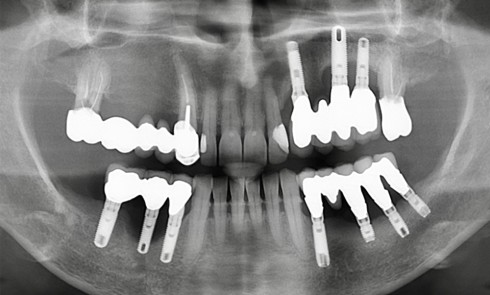

Le patient 54 ans Parodontite traitée en 2015 stabilisée, puis plusieurs épisodes d’activation sur les dernières années Prise en charge...